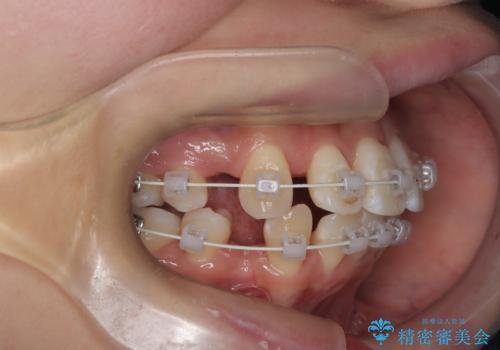

今回の矯正治療では、まず計画通り上下左右の小臼歯4本を抜歯し、八重歯や正中のズレを解消するための十分なスペースを確保しました。装置には、目立ちにくい白いブラケットとワイヤーを使用した審美ワイヤー矯正を採用。

抜歯によってできたスペースを利用し、

八重歯: 突出していた八重歯を歯列内に誘導し、デコボコを解消しました。

正中のズレ: 歯を左右対称に移動させることで、上下の歯の中心線を正確に合わせ、顔全体のバランスも改善しました。